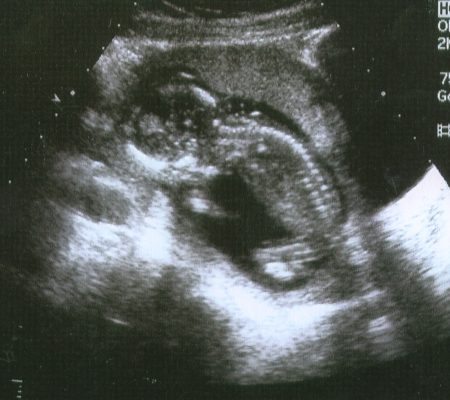

The initial ultrasound was also abnormal. The lady performing the test kept making perplexed faces and that was very frustrating to endure when they aren’t allowed to answer questions or tell you that something is wrong. After she finished she led me to a private room and said that a doctor would call on the telephone shortly. That is how I found out my baby would die. Alone in a strange room, talking on the phone with a doctor that I had never met nor never would, as he’s recommending an abortion.

I chose to continue the pregnancy. They did not know specifically what would be wrong and I was okay with that. They did, however, tell me that I would likely miscarry within the first 16 weeks, but they were wrong.

Each ultrasound there was another thing wrong. He’s too small. The amniotic fluid is low. He’s missing part of his brain……and so on. I stopped making those visits for a little while because it just became too much. And then when I did go back he had grown the part of his brain that was previously missing. I declined an amniocentesis because it didn’t matter to me what he had and I didn’t want to increase my risk of having a miscarriage.